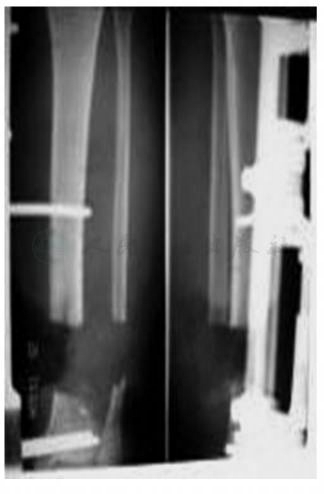

2007年4月17日患者因“被重物挤压伤致左小腿出血、畸形3小时”以“胫腓骨开放骨折(左,Gustilo Ⅲb)”急诊入院(图1)。入院后即行胫腓骨开放骨折清创术、开放复位接骨板螺丝钉内固定术和自体游离皮片移植术。

图1 创伤后X线片